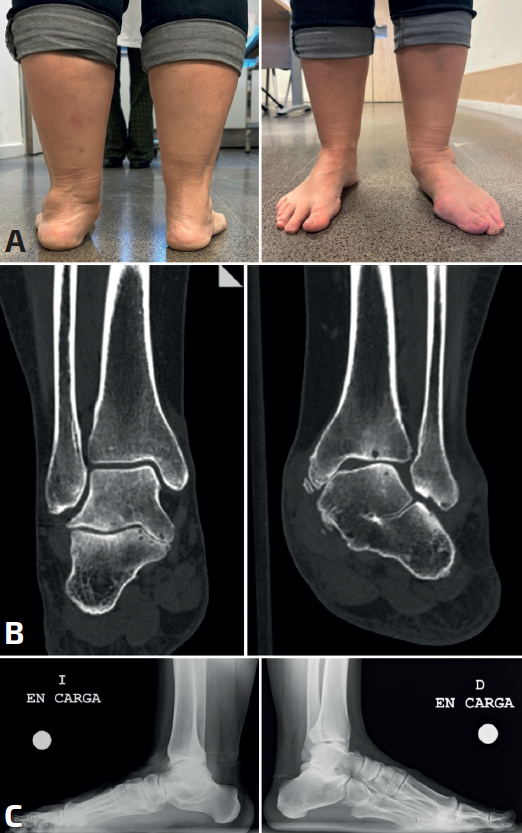

En la prueba de bloque de Coleman invertido (Figura 3), el pie del paciente se supina elevando medialmente el antepié con un bloque y manteniendo el talón y el borde lateral en contacto con el suelo. Si el talón valgo no se corrige, el retropié será rígido. Se puede observar además una disminución en la rotación externa normal de la tibia, reflejada por la ausencia de rotación hacia afuera de la rótula. Otra forma sencilla de evaluar un movimiento subtalar restringido es pedir al paciente que camine sobre los bordes externos de los pies, lo que le puede resultar difícil o incómodo. En el test de Fonseca o de elevación de un solo talón o de ambos si no es capaz (heel rise) (Figura 4), el talón debe ponerse en varo, debido a la rotación externa de la tibia por efecto del tibial posterior, efecto que cierra “la llave del mediopié”, pasando a un mediopié rígido propulsivo. Si el talón no se coloca en varo, indicaría así su rigidez. El test de Jack (Figura 3) tiene la misma función de demostrar una subastragalina móvil, un pie plano en carga recuperaría el arco a la dorsiflexión del hallux por el efecto de tensión de la fascia plantar (windlass).

Figura 4. Test de Fonseca o heel rise: elevación de un solo talón o de ambos si no es capaz. El talón debe tomar una posición en varo. Caso bilateral de coalición subastragalina: pie izquierdo valgo rígido, derecho ligero varismo.